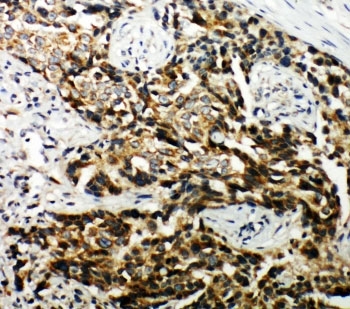

IHC-P: TSC1 antibody testing of human breast cancer tissue